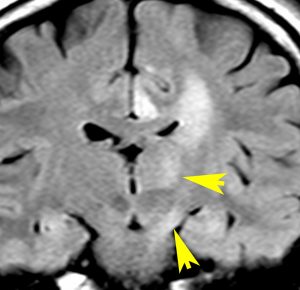

悪性転化 malignant transformation,膠芽腫への進展 progression

40代の患者さんです。夜間睡眠中の全般発作(症候性てんかん)で発症しました。フレア画像で左上前頭回に滲むような高信号領域(白い部分)がみられます。右側はガドリニウム増強MRIですが,全く増強されません。グレード2か3の星細胞腫あるいは乏突起膠腫を疑います。白く滲むような領域はよく見るとかなり広範囲に広がっています。

画像上では全摘出 gross total removalできて,病理診断は,退形成性乏突起星細胞腫 anaplastic oligoastrocytomaでした。IDH変異あり,1p/19q欠失なしです。現在の診断なら,退形成性星細胞腫 グレード3です。

手術後に54グレイの広範囲な局所放射線治療とテモゾロマイド化学療法を行いました。左の画像は放射線治療計画の時の線量分布図です。

5年後にいきなり激しい再発を生じました。再発部位は,放射線照射野外 out-of-fieldの前頭部帯状回でした。手術前に急速に増大して,画像所見も初回と全く違いました。摘出後の病理は,IDH1/2 wild type, 1p/19q intact, ATRX negative, MGMT met negative, MIB-1 40%という典型的な膠芽腫の所見でした。

この例とは異なって,退形成性星細胞腫の再発時には,IDH mutantのままの方が多いです。もしかすると先行した放射線誘発膠芽腫かもしれません。